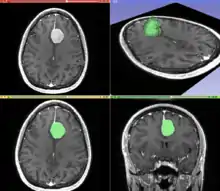

Segmentation

Segmentation is the process of partitioning an image into different meaningful segments. In medical imaging, these segments often correspond to different tissue classes, organs, pathologies, or other biologically relevant structures.[2] Medical image segmentation is made difficult by low contrast, noise, and other imaging ambiguities. Although there are many computer vision techniques for image segmentation, some have been adapted specifically for medical image computing. Below is a sampling of techniques within this field; the implementation relies on the expertise that clinicians can provide.